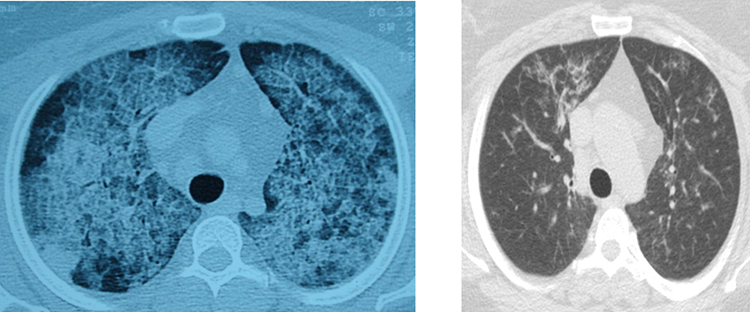

Pamukkale Üniversitesi Hastanesi Göğüs Hastalıkları Ana Bilim Dalı Öğretim Üyesi Prof. Dr. Göksel Altınışık Ergur, akciğerlerde yağ birikmesiyle ortaya çıkan hastalıkların akciğer yıkama yöntemiyle başarılı bir şekilde tedavi edildiğini bildirdi.

Hastalığın, kişinin kendi yağ ve proteinlerinin temizlenmesiyle görevli hücrelerdeki sorun nedeniyle akciğerlerdeki hava keseciklerinin birikmesi sonucu ortaya çıktığını aktaran Ergur, belirtilerin nefes darlığı, yorgunluk ve aşırı halsizlik olduğunu kaydetti.

Ergur, hastalığın çoğu zaman astımla karıştırıldığını, tanının ancak ileri tetkiklerle konulabildiğini ifade etti.